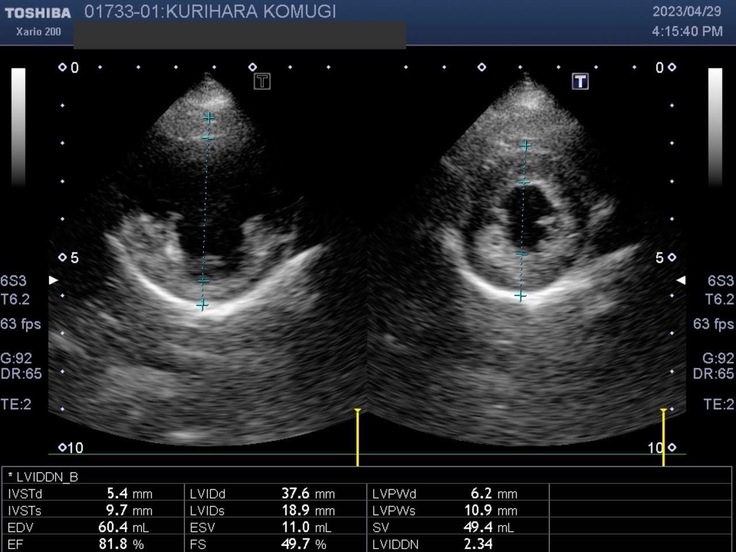

▽エコー写真

※かかりつけの動物病院からの掲載許可をいただいています。

※循環器専門病院からの掲載許可をいただいています